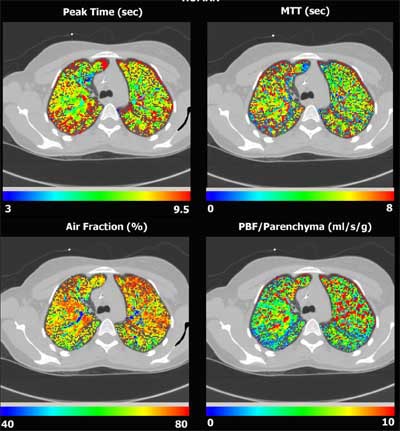

Perfusion imaging begins with a bolus of contrast injected at a fast .75 ml/kg into the vena cava, iohexal in animals and iodixanol (Visipaque) in humans (Amersham Health, Buckinghamshire, U.K.). The agents produce clearly delineated dye curves that can be analyzed to calculate mean transit times, arrival times, peak blood flow normalized to air tissue contents, and more.

![]() |

| Four-panel image shows human physiological maps superimposed onto a CT, demonstrating distribution of time to peak, mean transit time, air fraction and pulmonary blood flow, all based on a first-pass time attenuation analysis of a bolus of contrast agent. |